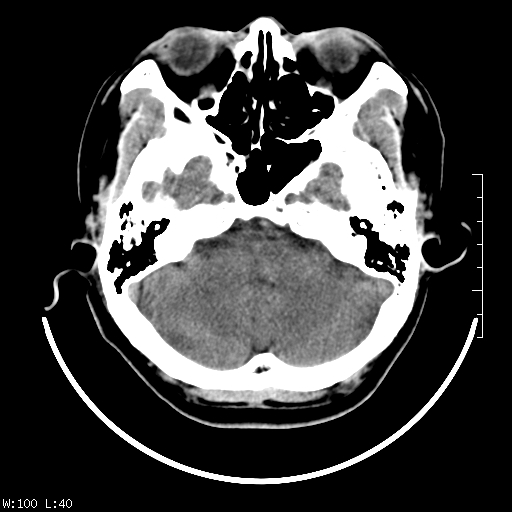

标题: CT22236:男,45,经常头痛。看看脑干正常吗? [打印本页]

标题: CT22236:男,45,经常头痛。看看脑干正常吗?

未见明显异常,建议ct增强或mri检查。

没见异常密度及形态改变啊,我认为是正常的。

颅脑ct轴位平扫颅内未见明确异常。

颅脑ct平扫未见明确异常,必要时mri检查。

颅脑ct平扫未见异常